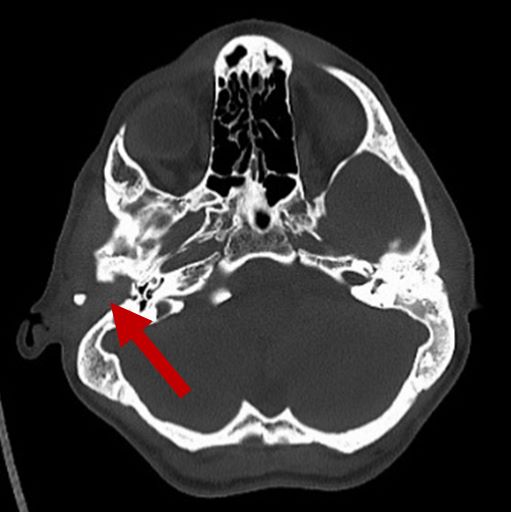

Airway obstruction

2D CT scan showing blocked airway

Radiographical features source 7